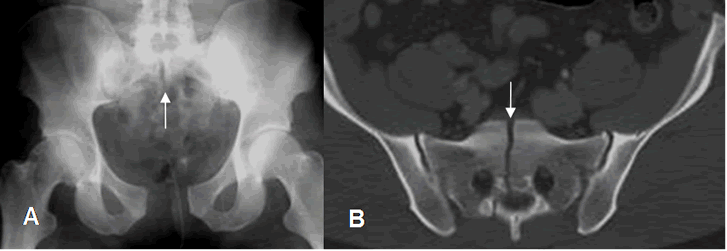

Fig 40. Trauma de pelvis. Compresión AP.

A: Rx AP. Fracturas oblicuas de los ramos ilio e isquiopúbico.

Fig 41. Trauma de pelvis. Compresión AP.

A: Rx AP. Interrupción de la línea ilioisquial, por fractura.

B: TAC axial. Fractura del ramo iliopúbico.